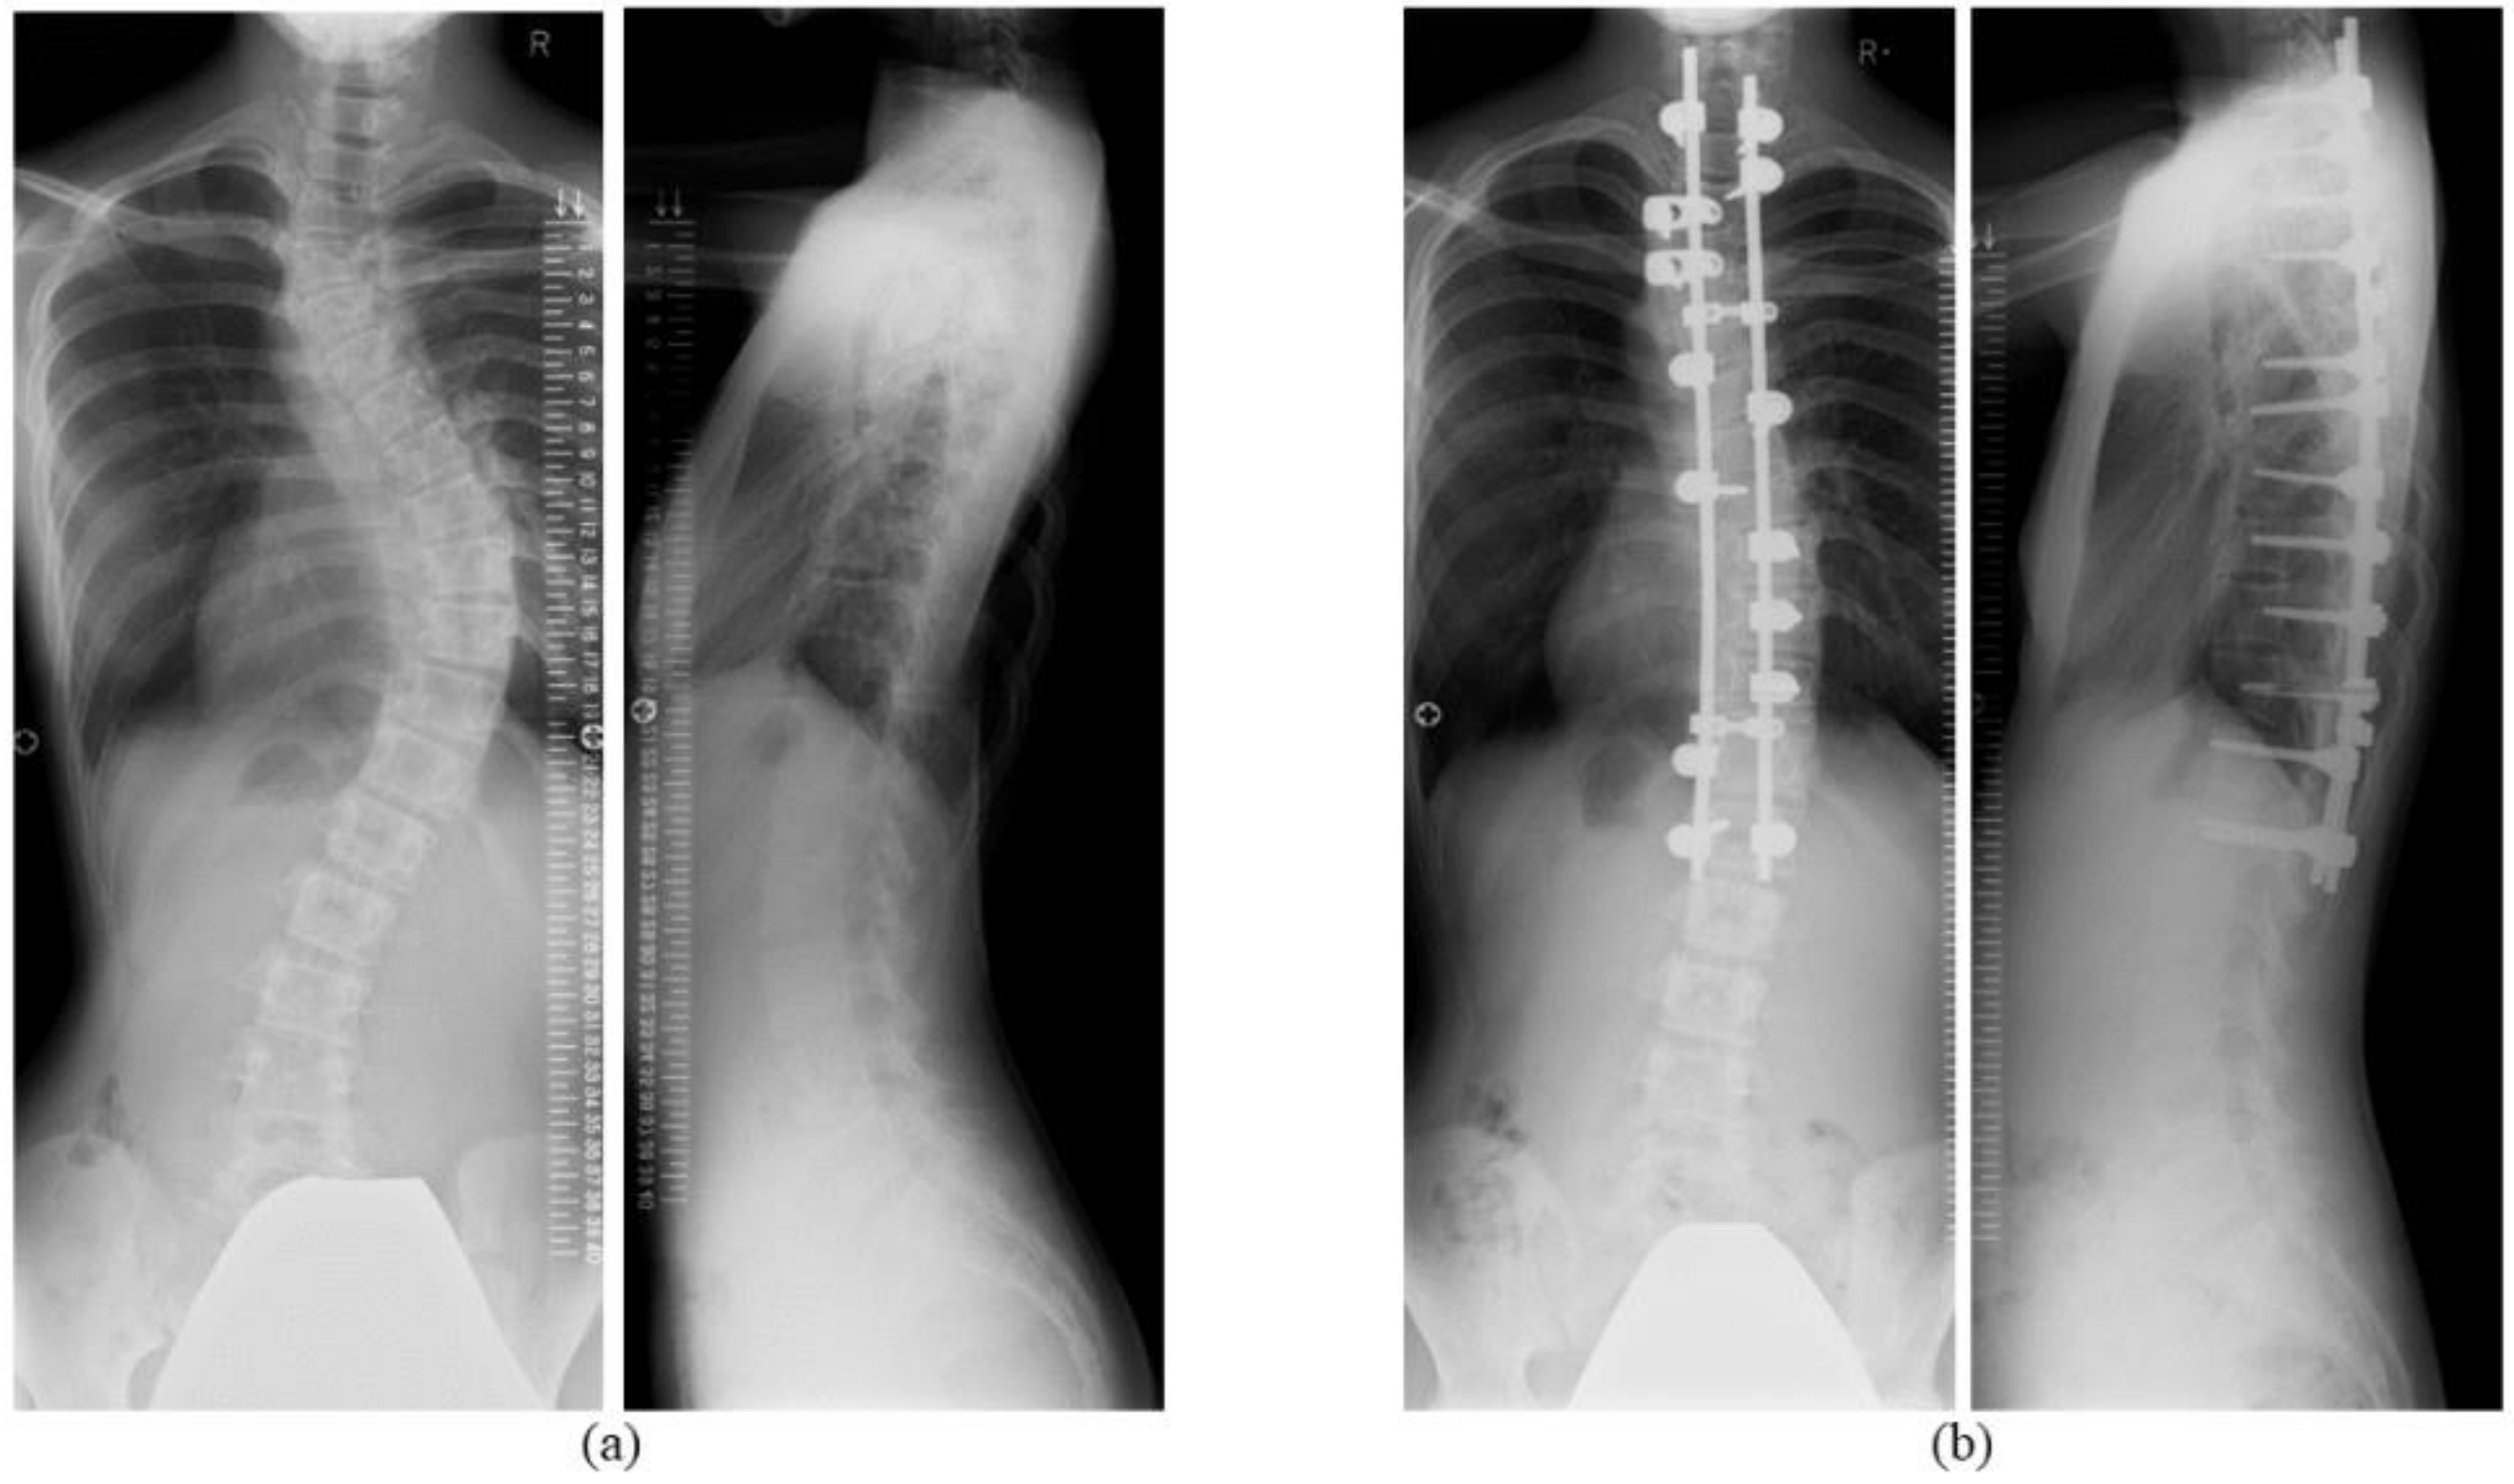

| Cobb angle of main thoracic curve, ° | 59.4 ± 3.0 | 23.4 ± 1.8 ** | 25.8 ± 1.7 ** | 25.6 ± 1.7 ** |

| Correction rate of Cobb angle (main thoracic curve), % | N/A | 60.8 ± 2.2 | 56.3 ± 2.5 | 56.8 ± 2.2 |

| Cobb angle of lumbar curve, ° | 40.5 ± 4.0 | 18.6 ± 2.5 ** | 17.9 ± 2.2 ** | 18.8 ± 2.3 ** |